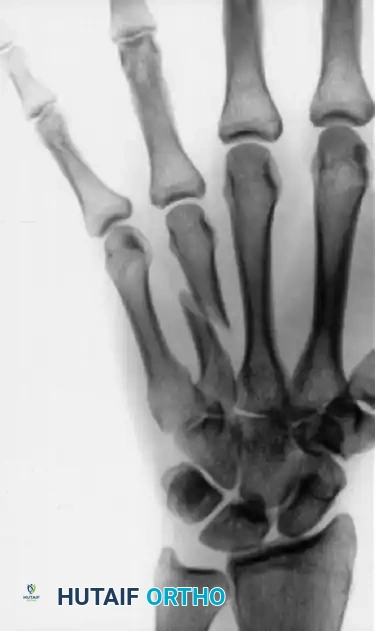

Management of Extra-Articular Thumb Base Fractures

Extra-articular fractures of the first metacarpal base (epibasal fractures) are common and often present with significant apex-dorsal angulation due to the unopposed pull of the APL.

Consider the case of an extra-articular thumb base fracture with 35 degrees of apex dorsal angulation in a 65-year-old male. While up to 30 degrees of angulation can sometimes be tolerated due to the compensatory mobility of the CMC joint, greater angulation requires reduction to prevent symptomatic hyperextension of the metacarpophalangeal (MCP) joint.

Surgical Steps for Epibasal Fractures:

1. Perform closed reduction using longitudinal traction and direct volar-directed pressure over the fracture apex.

2. Secure the reduction with K-wire fixation driven from the metacarpal shaft into the trapezium, bypassing the fracture site to provide a stable strut.

The following sequence illustrates the progression from injury to successful closed reduction and K-wire fixation into the trapezium: